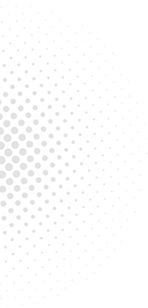

6��23��-6��29��������ר�ҳ���һ����

������鿴��ͼ���Ե���ʵ�ʳ���Ϊ��

6��23��-6��29�������dz���ר�ҽ���

6��23��

6��25��

6��26��

6��27��

6��28��

6��29��